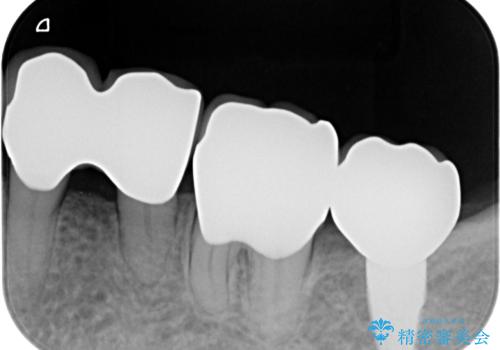

歯周病の問題が解決したのち、歯の揺れを抑えるべくセラミッククラウンで連結補綴をおこなっています。

- 102.3万円 (再生療法 歯周ポケット除去手術 インプラント アバットメント セラミッククラウン×4 )費用は治療当時の料金となります

再生療法を行ったことで、抜歯をされてもおかしくなかった歯を、残すことができました。